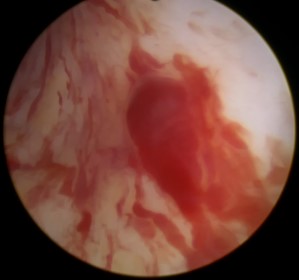

图三:镜下观察尿道异常扩张的血管